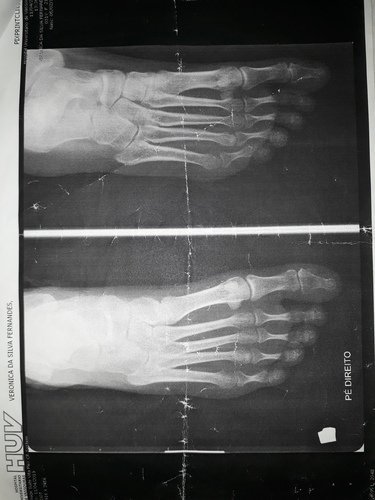

Polineuropatia sensitiva ,predominante axonal nos membros inferiores. Polineuropatia sensitivo motora axonal grave.